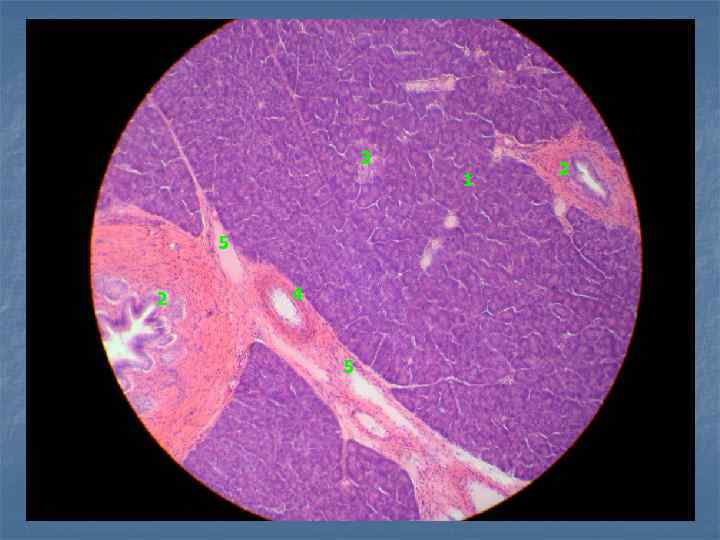

Пр. 1. Печень свиньи. Окраска: гематоксилин и пикрофуксин. Увеличение: малое. междольковые прослойки соединительной ткани печеночные балки центральная вена

5 4 2 3 1